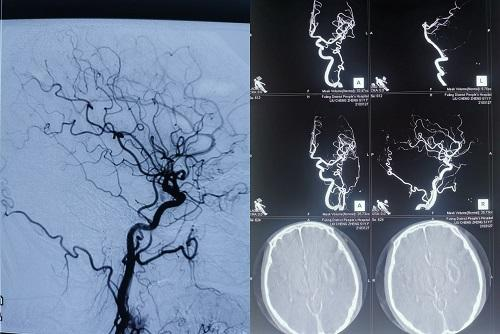

造影影像

患者刘某某,女性,53岁,因多次脑出血入院,为明确是否存在脑血管病变,患者及家属知情同意下,在我院神经外科夏先进主任的带领下,胡松林主治医师、郑媛文医师在3月31日行全脑血管造影术,手术顺利,各血管均获得良好显影,获得充足的诊治信息,有效指导了下一步的治疗策略。术中及术后患者无明显不适,各项生命体征平稳,患者及家属十分满意。